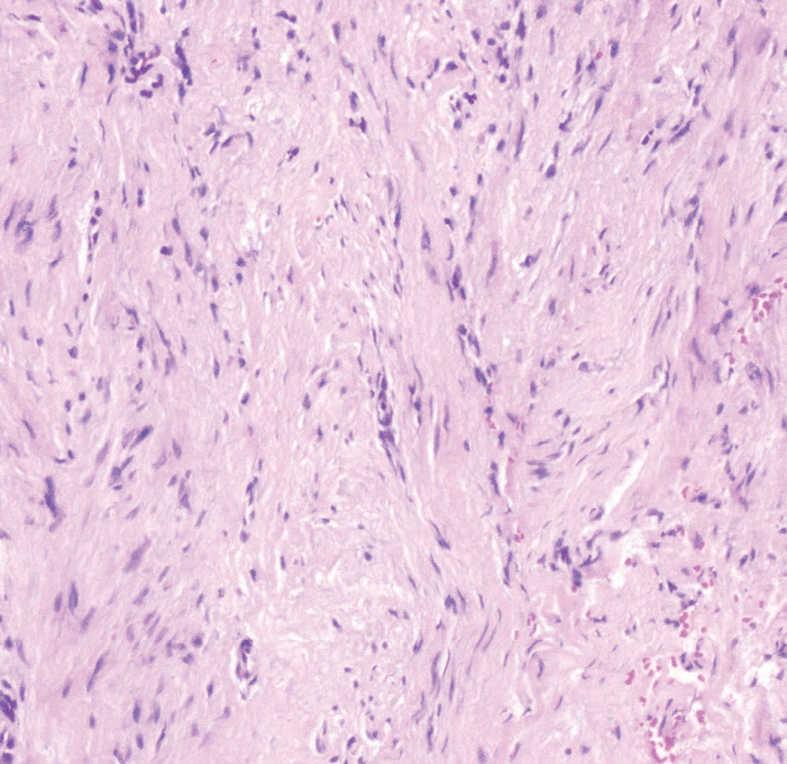

En la primera visita se realizó una analítica general, que no mostró hallazgos patológicos, y una serología viral, incluyendo virus exantemáticos, que resultó negativa. La radiografía de la mano sólo mostraba un engrosamiento focal de partes blandas, sin afectación ósea subyacente. Se revisaron las biopsias correspondientes a la lesiones extirpadas inicialmente (figs. 3-5).

Fig. 4.--La tumoración estaba compuesta por fascículos entrelazados de células fusiformes. (Hematoxilina-eosina, x100.)

El examen histopatológico correspondiente a la extirpación previamente realizada mostraba una proliferación mal delimitada localizada en la dermis y el tejido celular subcutáneo, que se extendía hasta la unión dermoepidérmica, compuesta por fascículos entrelazados de células fusiformes (figs. 3 y 4). No se observaban células ni mitosis atípicas. A mayor aumento, en el citoplasma de algunas de estas células se apreciaba la presencia de inclusiones intracitoplasmáticas eosinofílicas, algunas de localización perinuclear (fig. 5). No se realizó estudio inmunohistoquímico.

La histología es característica. La biopsia cutánea muestra una proliferación mal delimitada en dermis y tejido celular subcutáneo, compuesta por células fusiformes, que corresponden a fibroblastos y miofibroblastos. Estas células se disponen formando fascículos entrelazados, rodeados por una estroma de colágeno, que se extienden hasta la unión dermoepidérmica. Las células presentan un núcleo alargado. La epidermis suprayacente no se ve apenas alterada, pero puede presentar ligera hiperqueratosis o acantosis. No se observan atipia nuclear ni mitosis atípicas. A mayor aumento se observan inclusiones eosinofílicas intracitoplasmáticas en las células fusiformes, de localización yuxtanuclear. Estas inclusiones se tiñen de rojo con el tricrómico de Masson y de púrpura con la hematoxilina ácida fosfotúngstica 1-10. El examen mediante microscopia electrónica revela que los cuerpos de inclusión citoplasmáticos se componen de una mezcla de material electrón-denso granular y fibrilar, que corresponde a filamentos similares a la actina 9,12. Se han descrito en adultos casos de un tumor histológicamente similar, pero de localización extradigital 4. Los estudios de inmunohistoquímica muestran en su mayoría positividad a la actina en el citoplasma de las células fusiformes.